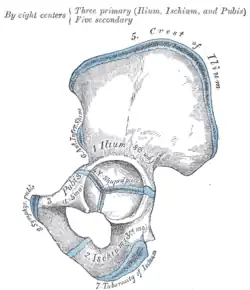

Das Acetabulum wird von Anteilen aller drei Knochen des Hüftbeins – Darmbein (Os ilium), Sitzbein (Os ischii) und Schambein (Os pubis) – gebildet. Bei Raubtieren ist darüber hinaus noch der Azetabularknochen (Os acetabulare) an der Bildung beteiligt, der Ende des zweiten Lebensmonats mit den übrigen Anteilen verschmilzt.

Das Acetabulum besteht aus einer halbmondförmigen Gelenkfläche (Facies semilunata), die bei Wiederkäuern zweigeteilt ist (Pars major und minor). Die Knorpelfläche ist beim Menschen nur etwa 2 Zentimeter lang und 0,3 Zentimeter dick.

In der Mitte ist das Acetabulum zur Hüftgelenksgrube (Fossa acetabuli) ausgehöhlt. In dieser Grube entspringt ein Band (Ligamentum capitis ossis femoris), das einen dünnen Zweig der Arteria obturatoria, die Arteria capitis femoris, aufnimmt. Diese ist an der arteriellen Versorgung des Oberschenkelknochens beteiligt. Das Band selbst hat keine mechanische Funktion. Die offene Seite des Halbmonds – beim Menschen vorn unten – wird als Incisura acetabuli („Hüftgelenkpfanneneinschnitt“) bezeichnet und durch ein Band (Ligamentum transversum acetabuli) verschlossen.

Der Rand des Acetabulums wird durch eine Gelenklippe (Labrum acetabuli) erhöht, die auf der umgebenden, knöchernen Gelenkpfanne (Limbus acetabuli) aufsitzt, so dass der Kopf des Oberschenkelknochens über seinen Äquator hinaus umfasst wird und daher ein Nussgelenk bildet. Die Gelenklippe (Labrum acetabulare) wird oftmals klinisch allerdings ebenfalls als Limbus bezeichnet.[2]